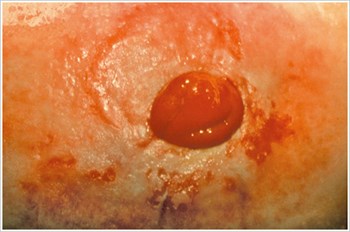

농피증 괴저(Pyoderma Gangrenosum)

설명/원인:

크론병이나 궤양성 대장염과 같은 염증성 장 질환(IBD) 환자에서 흔히 볼 수 있는 염증성 피부 질환.

조짐:

- 불규칙한 모양, 붉은색, 통증, 감염된 궤양, 빨간색에서 보라색으로 말린 가장자리; 다리, 엉덩이, 얼굴, 장루 주위 부위에 나타납니다.